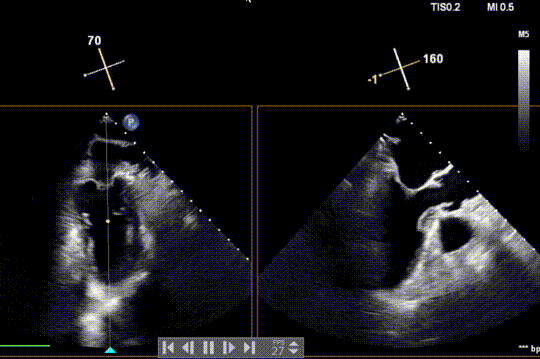

全麻后,二尖瓣夹合器系统在心前区的肋间切开3-4CM小切口,暴露心脏的心尖位置,送系统送入左心房,顺利到达病变二尖瓣区域。在经食道超声辅助下,术者通过反复评估二尖瓣反流位置、抓捕位置、反流程度,首先在2偏3区位置处于二尖瓣闭合线垂直进行巧妙夹合。在2区靠近3区位置处植入了1枚ValveClamp®MVC-IIf夹,最终评估评估反流降至轻度,平均跨瓣压差降至2mmHg,手术取得圆满成功。

术中超声(关键步骤)